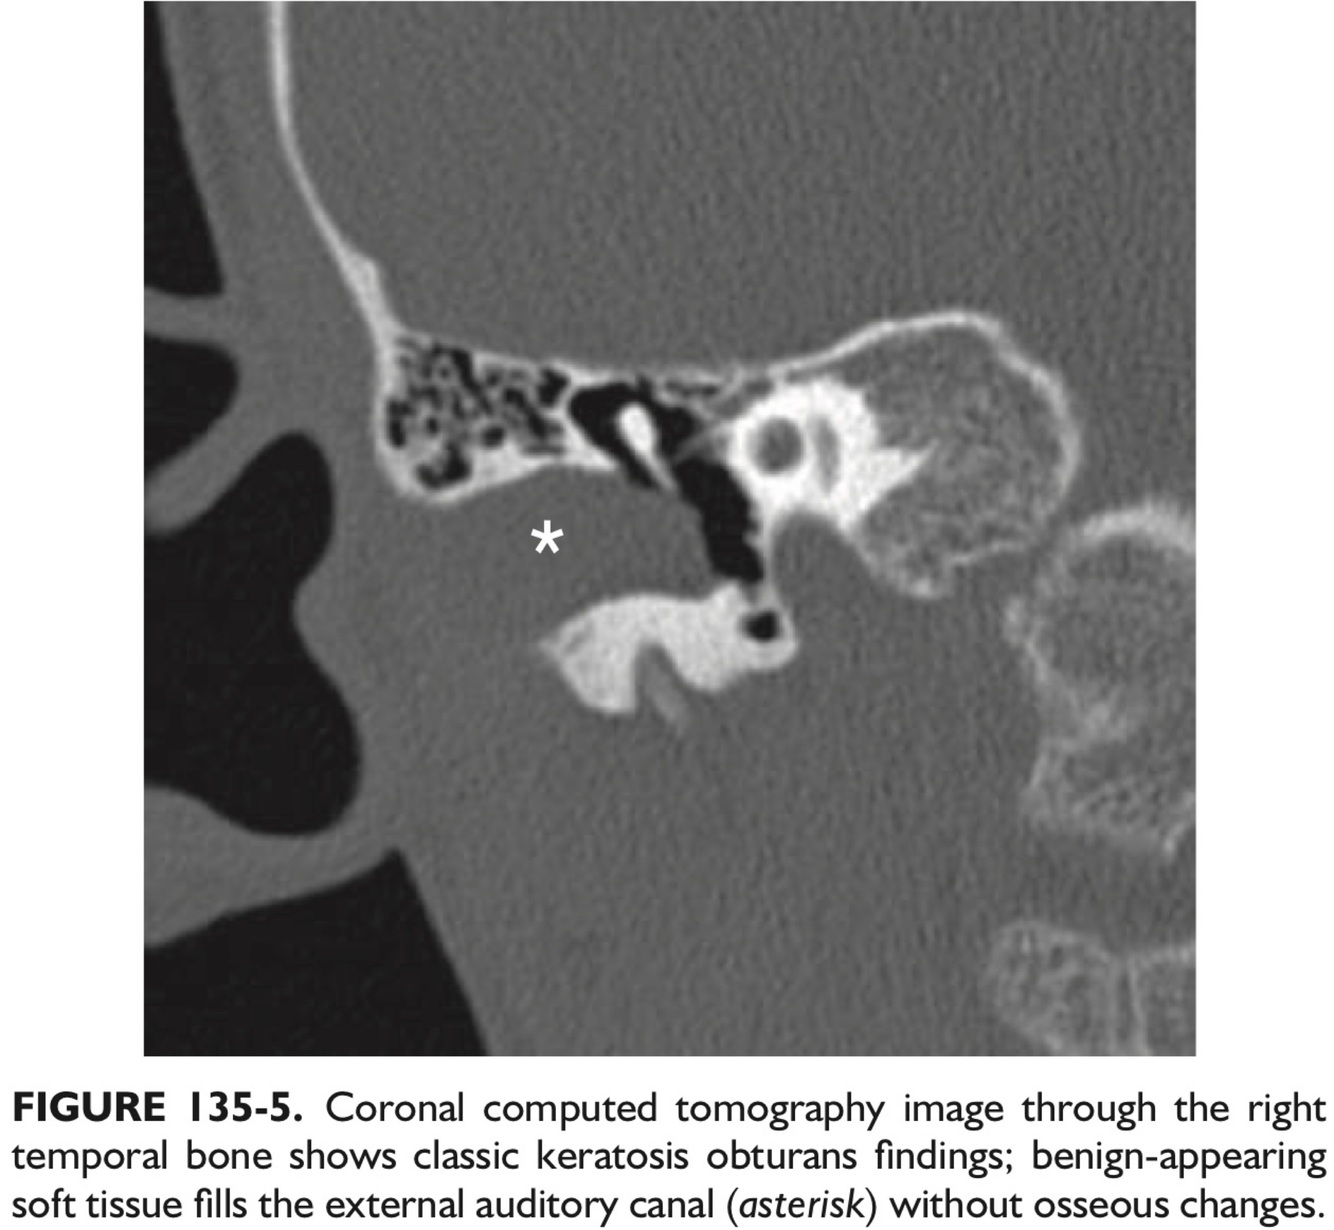

21

Q

Likely Diagnosis?

A

Keratosis obturans is an abnormal accumulation of keratinous debris w/in the EAC without erosive bony changes.

Imaging shows tissue filling the EAC, with an Intact TM.